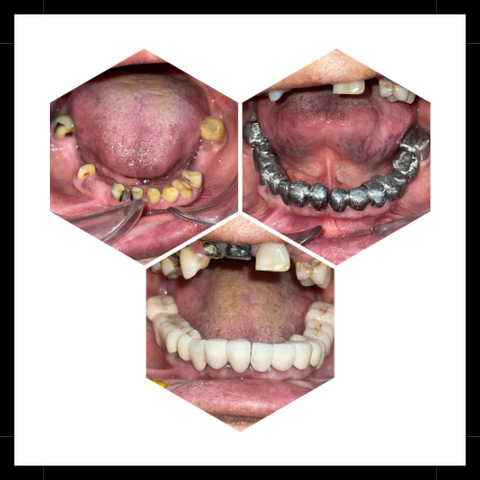

Treatment Gallery

Permanent replacement for missing teeth, providing a natural look & feel with long-lasting durability & improved oral function.